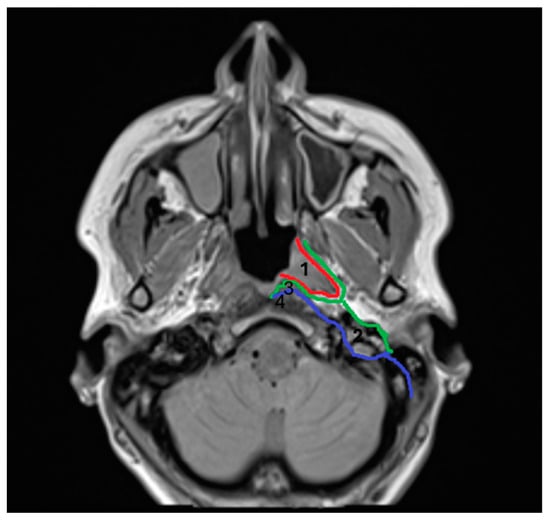

Sound knowledge of pertinent surgical anatomy is of paramount importance in order to access all involved neck spaces [1,2]. The pharyngeal mucosal space (PMS) has been described as the most superficial neck space, lying deep in the pharyngeal mucosa, anteromedially to the parapharyngeal space, and directly anterior to the retropharyngeal space. Its clinical significance has not been recognized until recently, through cross-sectional imaging studies. Anatomically, it represents the area of the nasopharynx and oropharynx on the inner side of the buccopharyngeal fascia. It is located between the pharyngeal mucosa (superficially) and the investing layer of the deep cervical fascia (pharyngobasilar fascia) (deep). The latter surrounds the pharyngeal constrictors. It extends from the skull base to the lower cricoid border, involving the naso-oro-hypopharynx. It is bordered by the superior constrictor muscles’ aponeurosis superiorly, where it merges with the middle layer of deep cervical fascia (Figure 1). PMS consists of five layers, forming the pharyngeal wall. From the internal to the external layers, they include the following: 1. mucosal membrane; 2. submucosa (containing loose areolar tissue, which facilitates deglutition, lymphoid tissue, and minor salivary glands); 3. dense pharyngobasilar fascia; 4. superior constrictor muscles of the pharynx; and 5. buccopharyngeal fascia (outer lining of the space). Dense connective tissue is present only on the deep surface of this layer (deep cervical fascia) [4,5,6,7,8]. Some studies suggest that the peritonsillar space is virtually part of the PMS [4,5,6]; however, more recent studies define them as separate spaces [8].

Figure 1. 1. Pharyngomucosal space (PMS), 2. parapharyngeal space (PPS), 3. retropharyngeal space (RPS), and 4. prevertebral space (PVS). Red line: pharyngobasilar fascia; green line: middle layer of deep cervical fascia; and blue line: deep layer of deep cervical fascia.